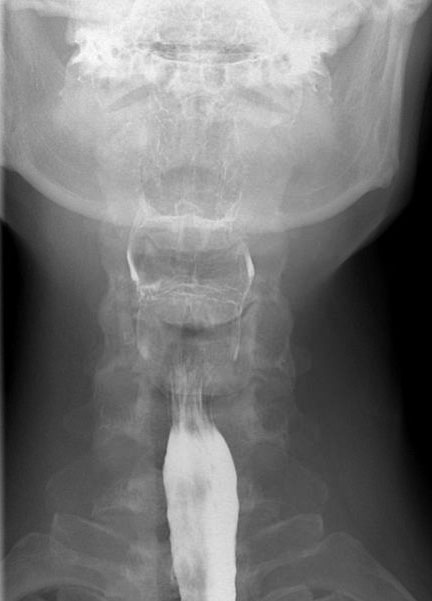

Tư thế thẳng (AP-view) quan trọng để đánh giá sự bất đối xứng.

Sau khi hoàn thành chuỗi hình ảnh giai đoạn hầu họng, cần theo dõi bolus thuốc cản quang toàn bộ đường đi xuống đến chỗ nối thực quản-dạ dày.